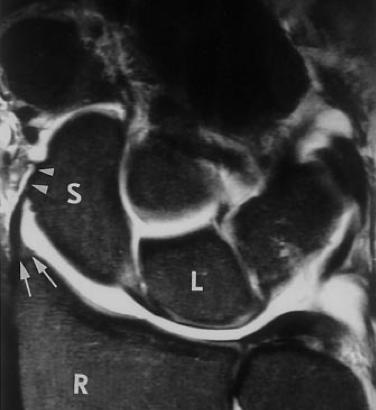

앞쪽의 경우 Radius 와 Ulna 와 수근골을 연결하는 단단한 인대들이 구성되어 있고

RSC 는 손목 안정화에 주요한 구조물 입니다. (Proximal row carpectomy 후에도 살리는 구조물 입니다.)

없으면 척골쪽으로 수근골들이 모두 빠지기 쉽습니다.